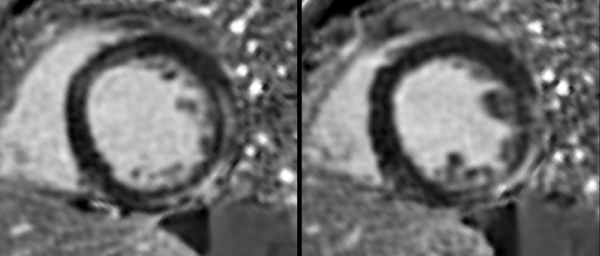

Myocarditis: CMR work-up.